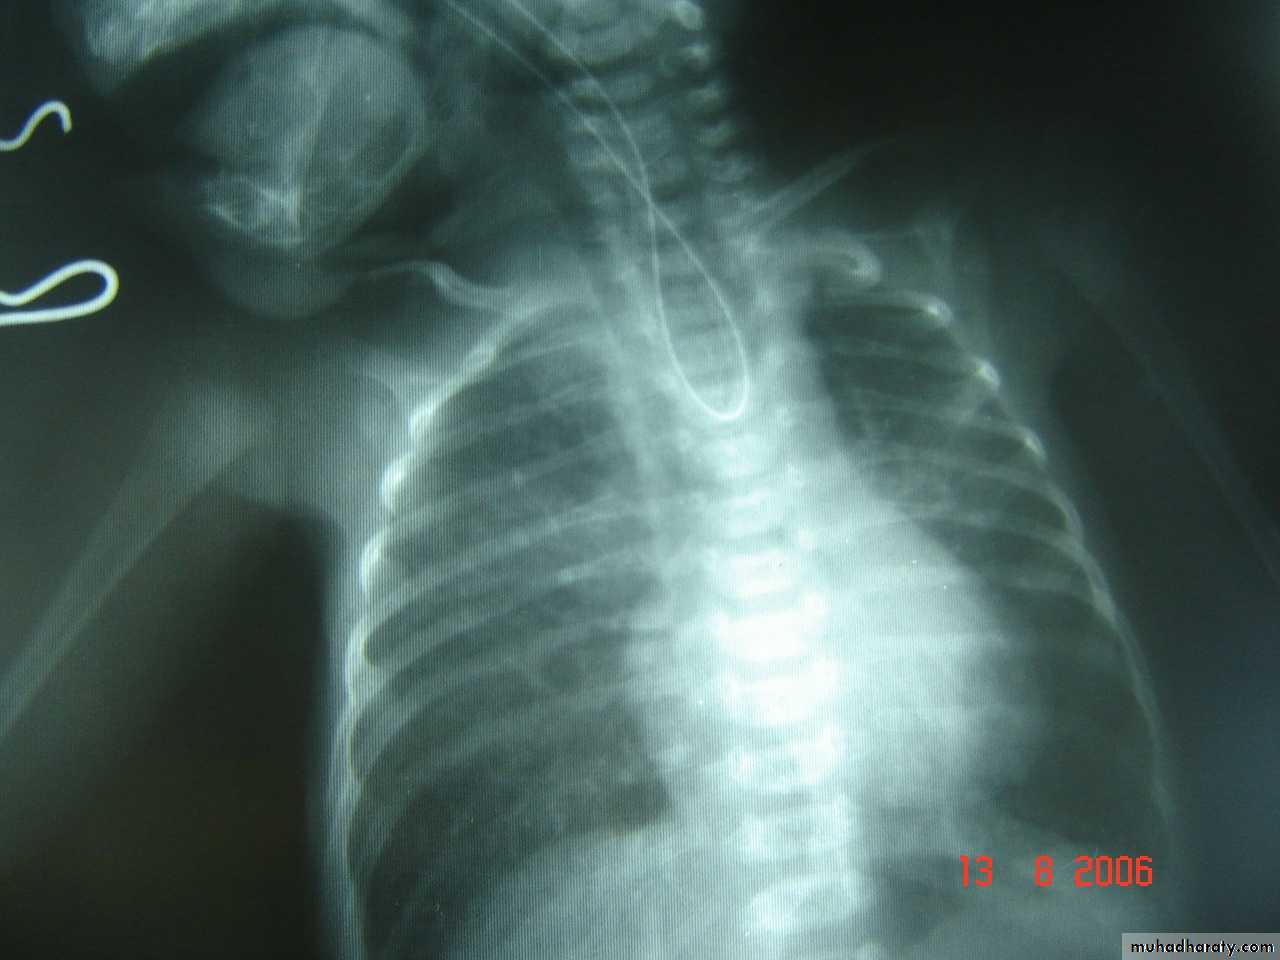

Respiratory Distress in the NewbornFirst photo:

Diagnosis: eventration of diaphragmDescription: mild dextrocardia – recurrent chest infection – diaphragm is present

mild distress - 7 months age baby – less number of intestinal loops in the chest

there is lung tissue in the chest - Paradoxical movement of the diaphragm.

Treatment: plication of the hemi-diaphragm (through thoracic approach).